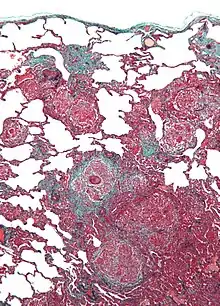

| Micrograph of hypersensitivity pneumonitis, the histologic correlate of bird fancier's lung. Lung biopsy. Trichrome stain. | |

Bird fancier's lung (BFL), also known as bird breeder's lung, is a type of hypersensitivity pneumonitis. It can cause shortness of breath, fever, dry cough, chest pain, anorexia and weight loss, fatigue, and progressive pulmonary fibrosis (the most serious complication). It is triggered by exposure to avian proteins present in the dry dust of droppings or feathers of a variety of birds. The lungs become inflamed, with granuloma formation. It mostly affects people who work with birds or own many birds.

BFL causes inflammation of the alveoli in the lungs. Avian proteins include mucins and antibodies, which stimulate a significant immune response from the body.[3] The lungs become inflamed, with granuloma formation. It can take many years of exposure to cause BFL, with an average of 1.6 years to cause acute disease, and 16 years to cause chronic disease.[2]

Lung biopsy usually reveals non-necrotizing granulomatous inflammation.[7] It also shows "foamy" macrophages and crystals of oxalic acid.[3] Hyperplasia tends to occur in type 1 pneumocytes and not in type 2 pneumocytes.[3]